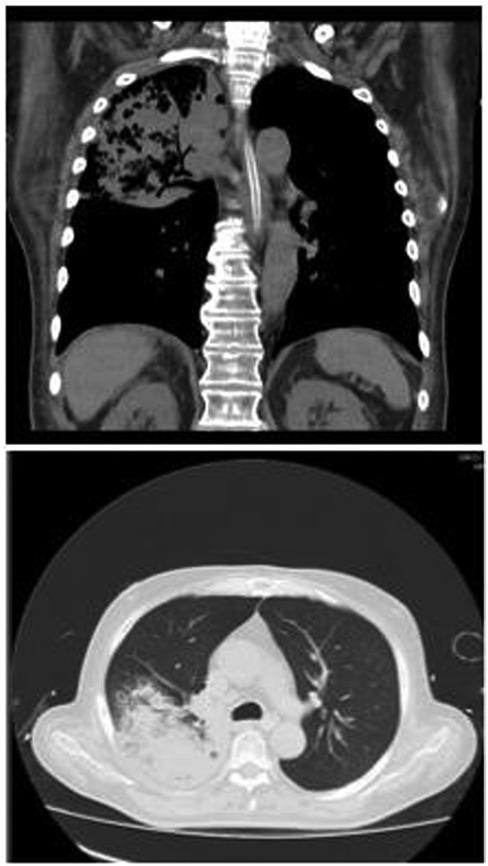

A 71-year-old man with diabetes mellitus and dysphagia consequent to a stroke presented with 3 days of productive cough associated with dyspnoea, followed by intermittent altered consciousness. He was admitted to the emergency room with irregular breath pattern and signs of imminent respiratory failure; he required orotracheal intubation and vasoactive support. On admission (Table 1), the laboratory results showed leucocytosis with left-shift neutrophilia, increased creatinine and urea nitrogen levels, uncompensated respiratory acidosis and moderate oxygenation disorder. Chest X-ray and high-resolution computed tomography (HRCT) were requested, showing a consolidation in the upper lobe with involvement of the apical and posterior segments (Figure 1).

High-resolution computed tomography at the second day of hospital stay.